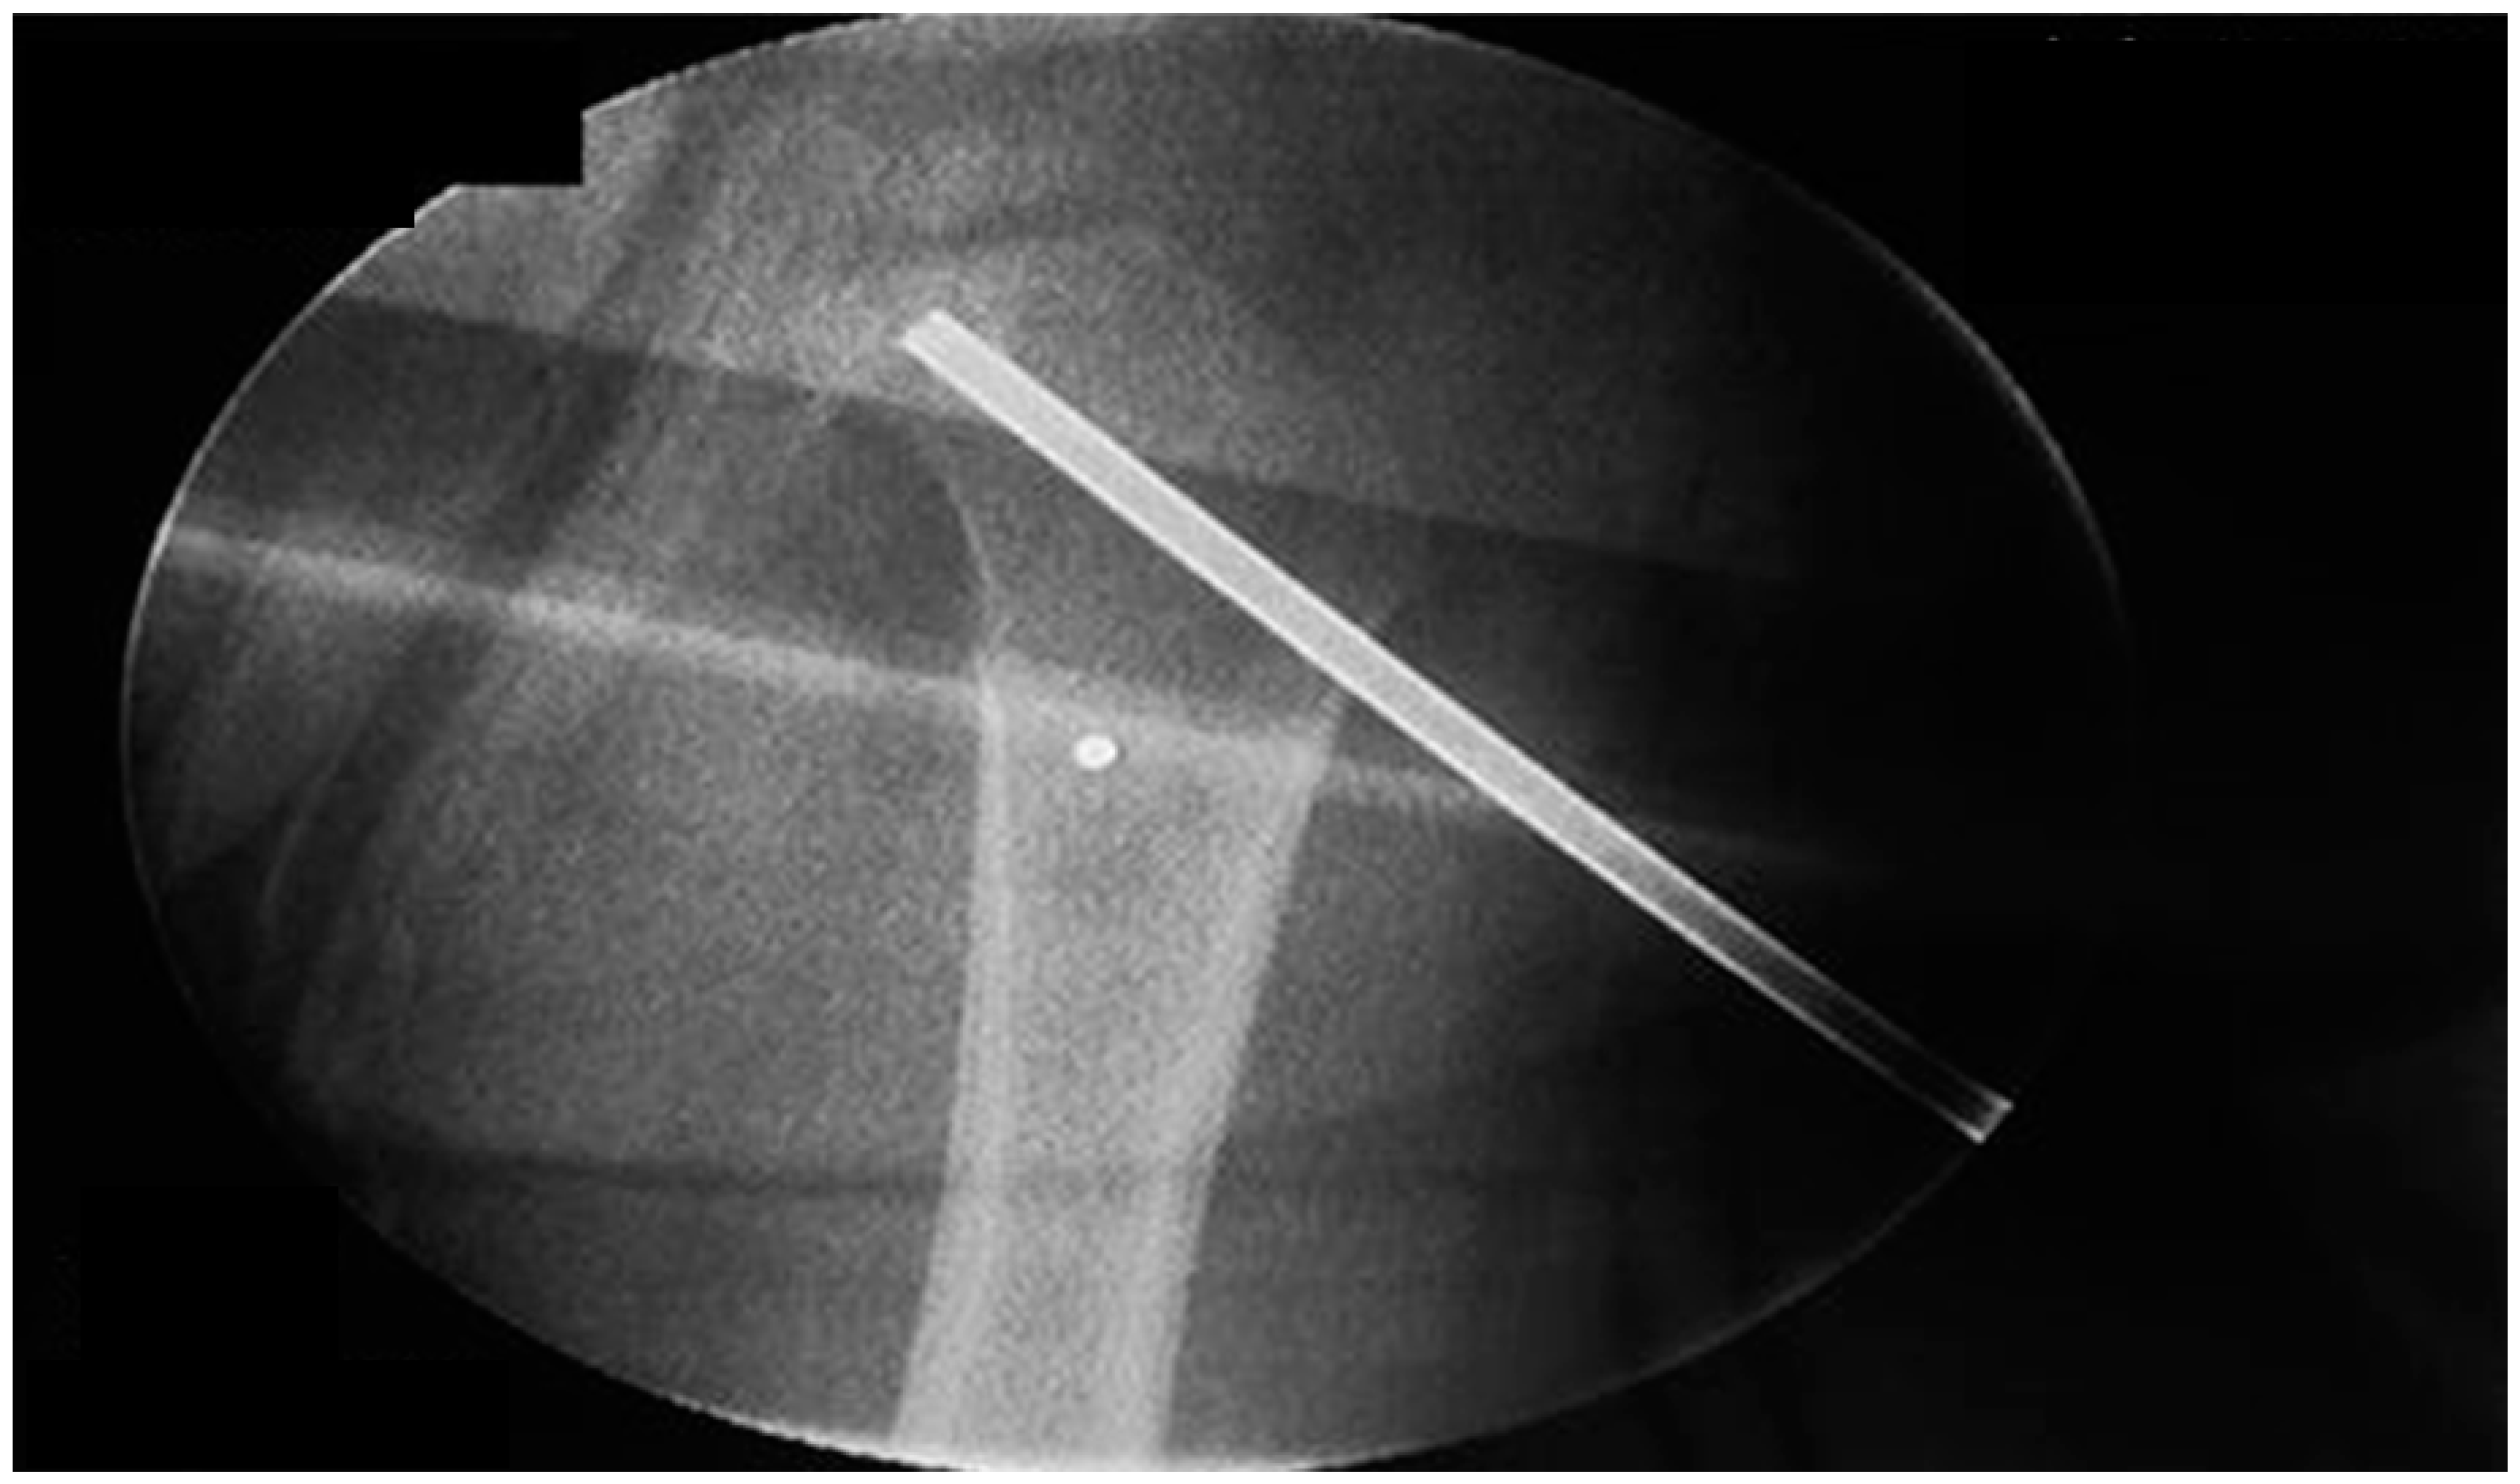

:1. Case Presentation